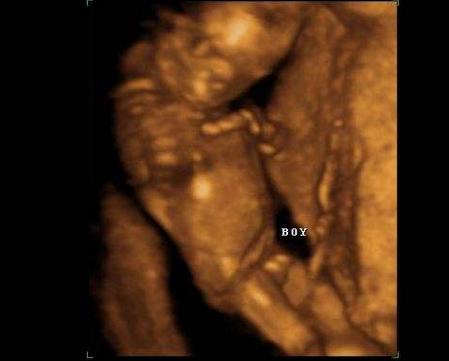

从医学的角度上来说,女性怀孕4个月之后就可以在b超检查中看出胎儿的性别了。因为4个月大的时候男孩和女孩的差别已经很明显了。随着你孕期的进展,这种差别会变得更加容易辨识。不过有一个前提就是,医生在检查的时候可以看到胎儿的关键部位。如果你的宝宝周围包裹着足够的羊水,而且他的脚也没有别在两条腿中间,那么孕晚期通过b超的数据通常能鉴别出胎儿的性别。

超看胎儿性别准不准,跟胎儿生殖器的发育一样,有一个渐进的过程。只有从你怀孕11周(80天)左右开始,不同性别的胎儿外表上才开始显现出差异。在怀孕4个月,也就是20周之后,b超检查看胎儿性别基本是没有差错的。

3、看孕后期b超数据

孕后期b超单中,双顶径减去股骨长的值大于2,男宝宝可能性大,值小于2,女宝宝可能性大。